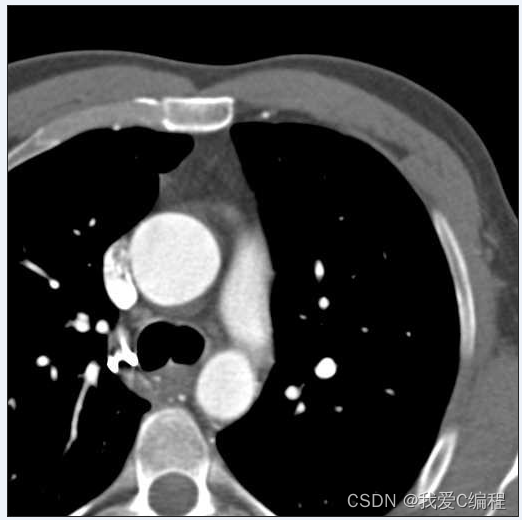

3.部分仿真截图